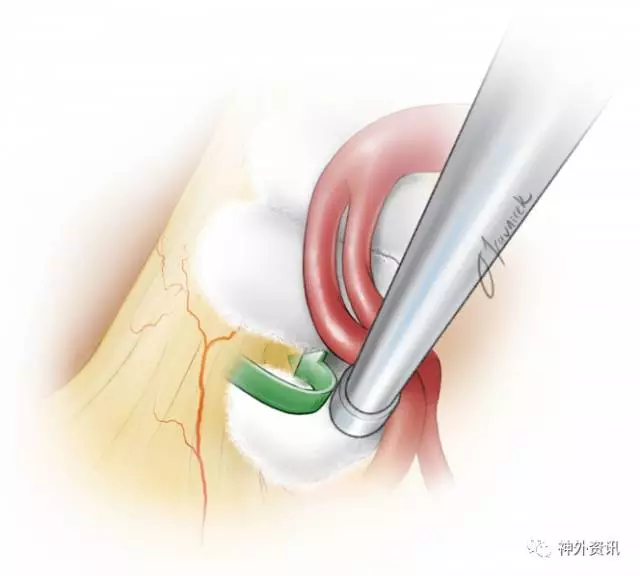

图11. 将切碎的Teflon置于神经和责任血管之间:通常是游离动脉,并在REZ区沿神经平行置入Teflon,以防止血管压迫REZ区及整个三叉神经脑池段。

笔者用撕碎的Teflon棉团来防止神经与血管的接触。考虑到植入物术后移位的风险,应避免使用未撕碎的Teflon棉片。Teflon棉团置入后沿着神经向前推动,这种方法让这些小片植入物符合动脉的形状,从而尽可能降低Teflon棉团迟发性移位的分险。

图12. 笔者特意在三叉神经肩部及腋内侧塞入一块teflon棉垫,防止血管与REZ区或脑干之间的任何接触。